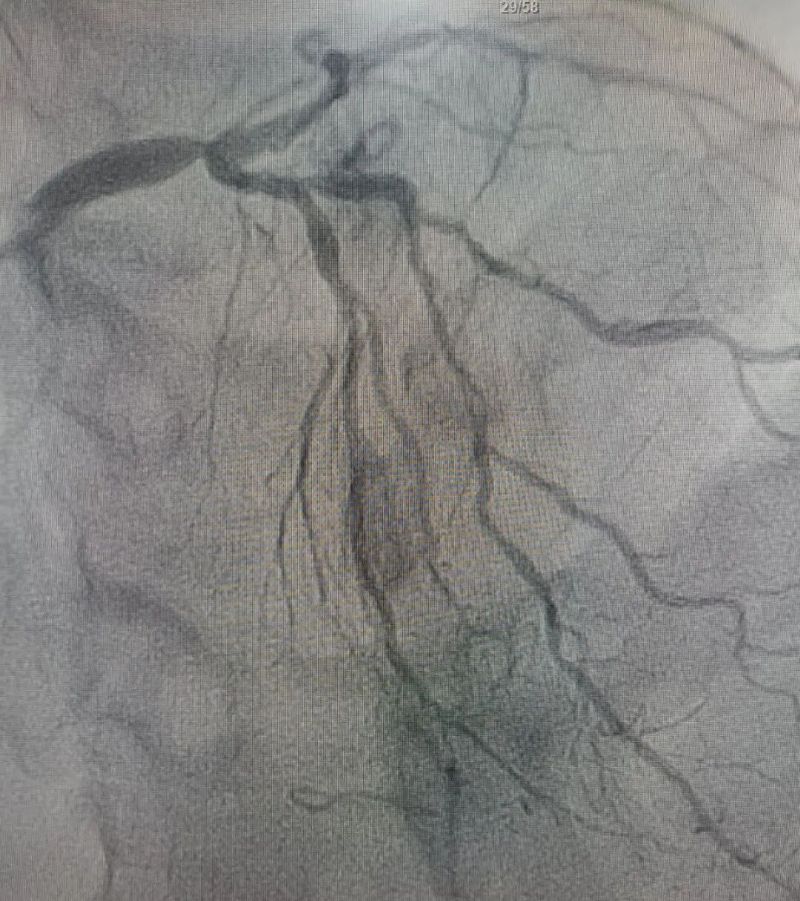

术中造影显示,左主干至前降支近段重度狭窄——这正是导致心脏缺血、诱发室颤的“罪魁祸首”。主动脉球囊反搏植入、球囊扩张、支架植入......介入团队精准操作,一气呵成。堵塞的血管顺利开通,血流重新涌动,这颗一度濒临停跳的心脏终于重获生机。

冠状动脉造影图

术前 (左主干至前降支近段重度狭窄)

术后(左主干至前降支近段原狭窄消失)